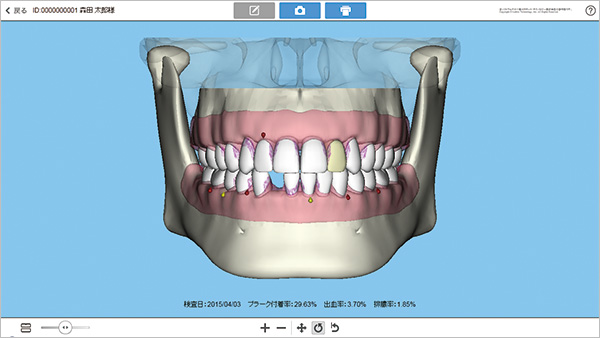

口腔状態

患者さんの口腔状態をイラストで分かりやすく表現。実際の撮影画像との比較もできます。また、「DOC-5」のカルテ情報とも双方向でつながります。

歯周検査

「Chirpy」を用いて入力した歯周検査結果を、グラフィカルに表示できます。また、「DOC-5」のカルテ情報と合わせて連動できます。

トリニティコア プロの画面

トリニティコア プロ